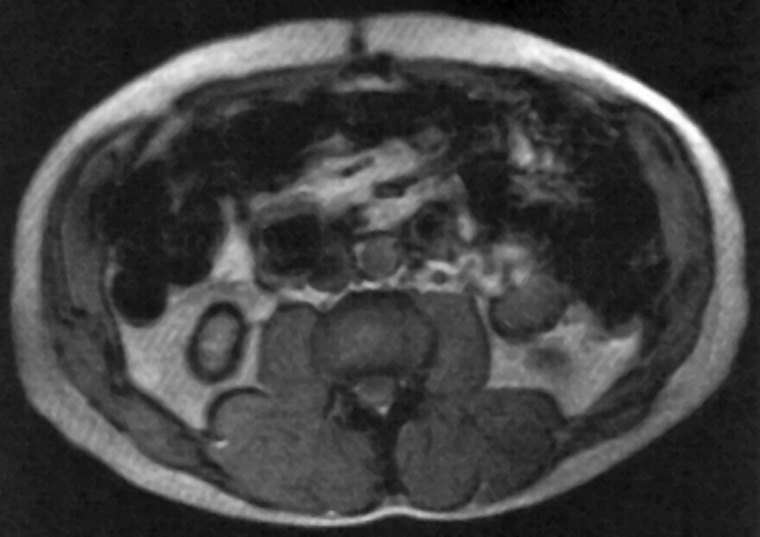

Figura 17-05:

Susceptibility artifacts created by ingested ferromag­netic particles used as an oral con­trast agent. Because the concentration of the particles is too high, the local mag­ne­tic field is disturbed and image arti­facts are created.